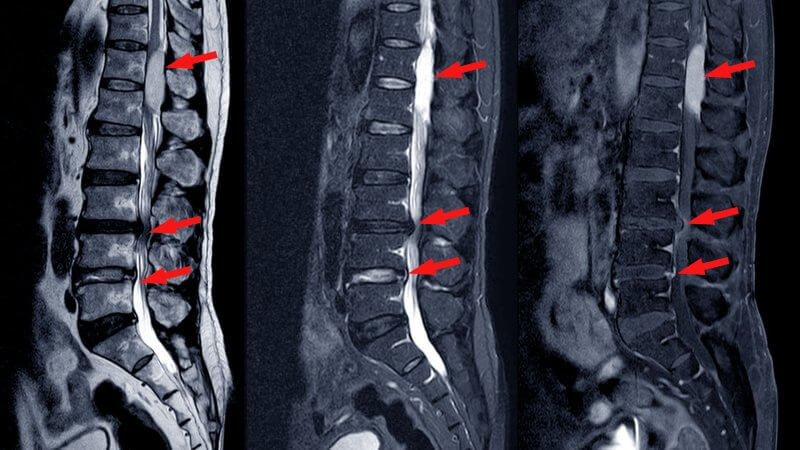

Imaging tests include:

- Magnetic resonance imaging (MRI) – provides detailed views of the spinal canal, nerve compression, discs, and ligaments.